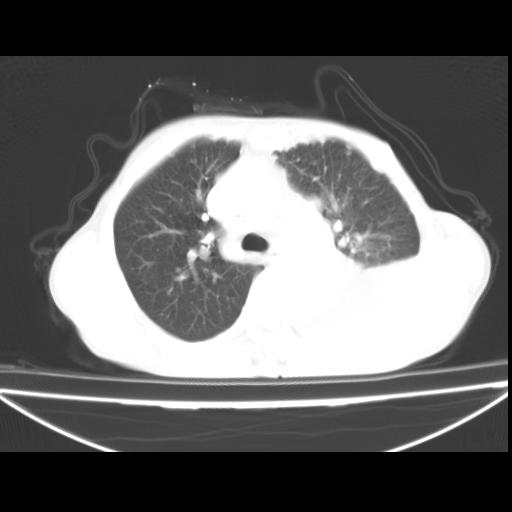

以下是引用随光逐影在2010-3-24 19:15:00的发言:[br]结合病史,考虑双肺及纵隔淋巴结多发转移、左侧胸膜转移并左侧大量胸水,左下肺膨胀不全。

以下是引用zxl51642在2010-3-24 18:49:00的发言:[br]结合乳腺癌术后病史,考虑双肺及纵隔淋巴结多发转移、左侧胸膜转移并左侧大量胸水、左下肺膨胀不全。